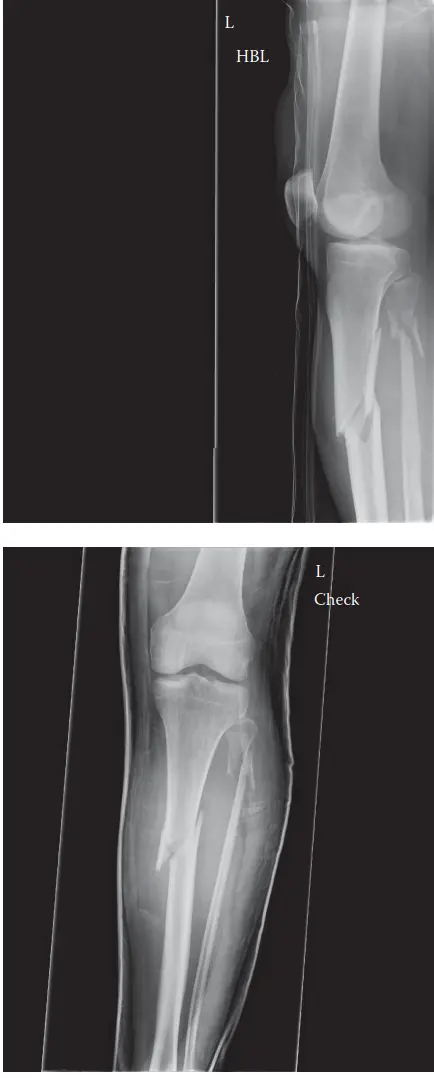

الأشعة السينية (X-ray)

تُعد الأشعة السينية هي الخطوة الأولى في التصوير. يتم التقاط صور من الأمام والخلف (AP) ومن الجانب (Lateral) للساق بأكملها، بما في ذلك مفصلي الركبة والكاحل للتأكد من عدم وجود إصابات أخرى.

- النتائج: في حالة مريضنا، كشفت الأشعة السينية عن كسر ظنبوبي معقد ومتفتت (متعدد الشظايا) في منتصف الجزء السفلي من الساق، مع انحراف أمامي (25-30 درجة) وانحراف خارجي (15-20 درجة)، وقصر بمقدار 2 سم. لوحظ وجود قطعة عظمية كبيرة على شكل فراشة، وكانت عظمة الشظية سليمة.